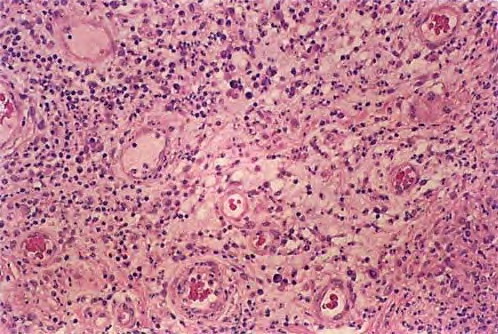

Herpes simplex = العقبول البسيط

Herpes simplex = العقبول البسيط OLYMPUS DIGITAL CAMERA OLYMPUS DIGITAL CAMERA OLYMPUS DIGITAL CAMERA OLYMPUS DIGITAL CAMERA OLYMPUS DIGITAL CAMERA OLYMPUS DIGITAL CAMERA OLYMPUS DIGITAL CAMERA OLYMPUS DIGITAL CAMERA OLYMPUS DIGITAL CAMERA